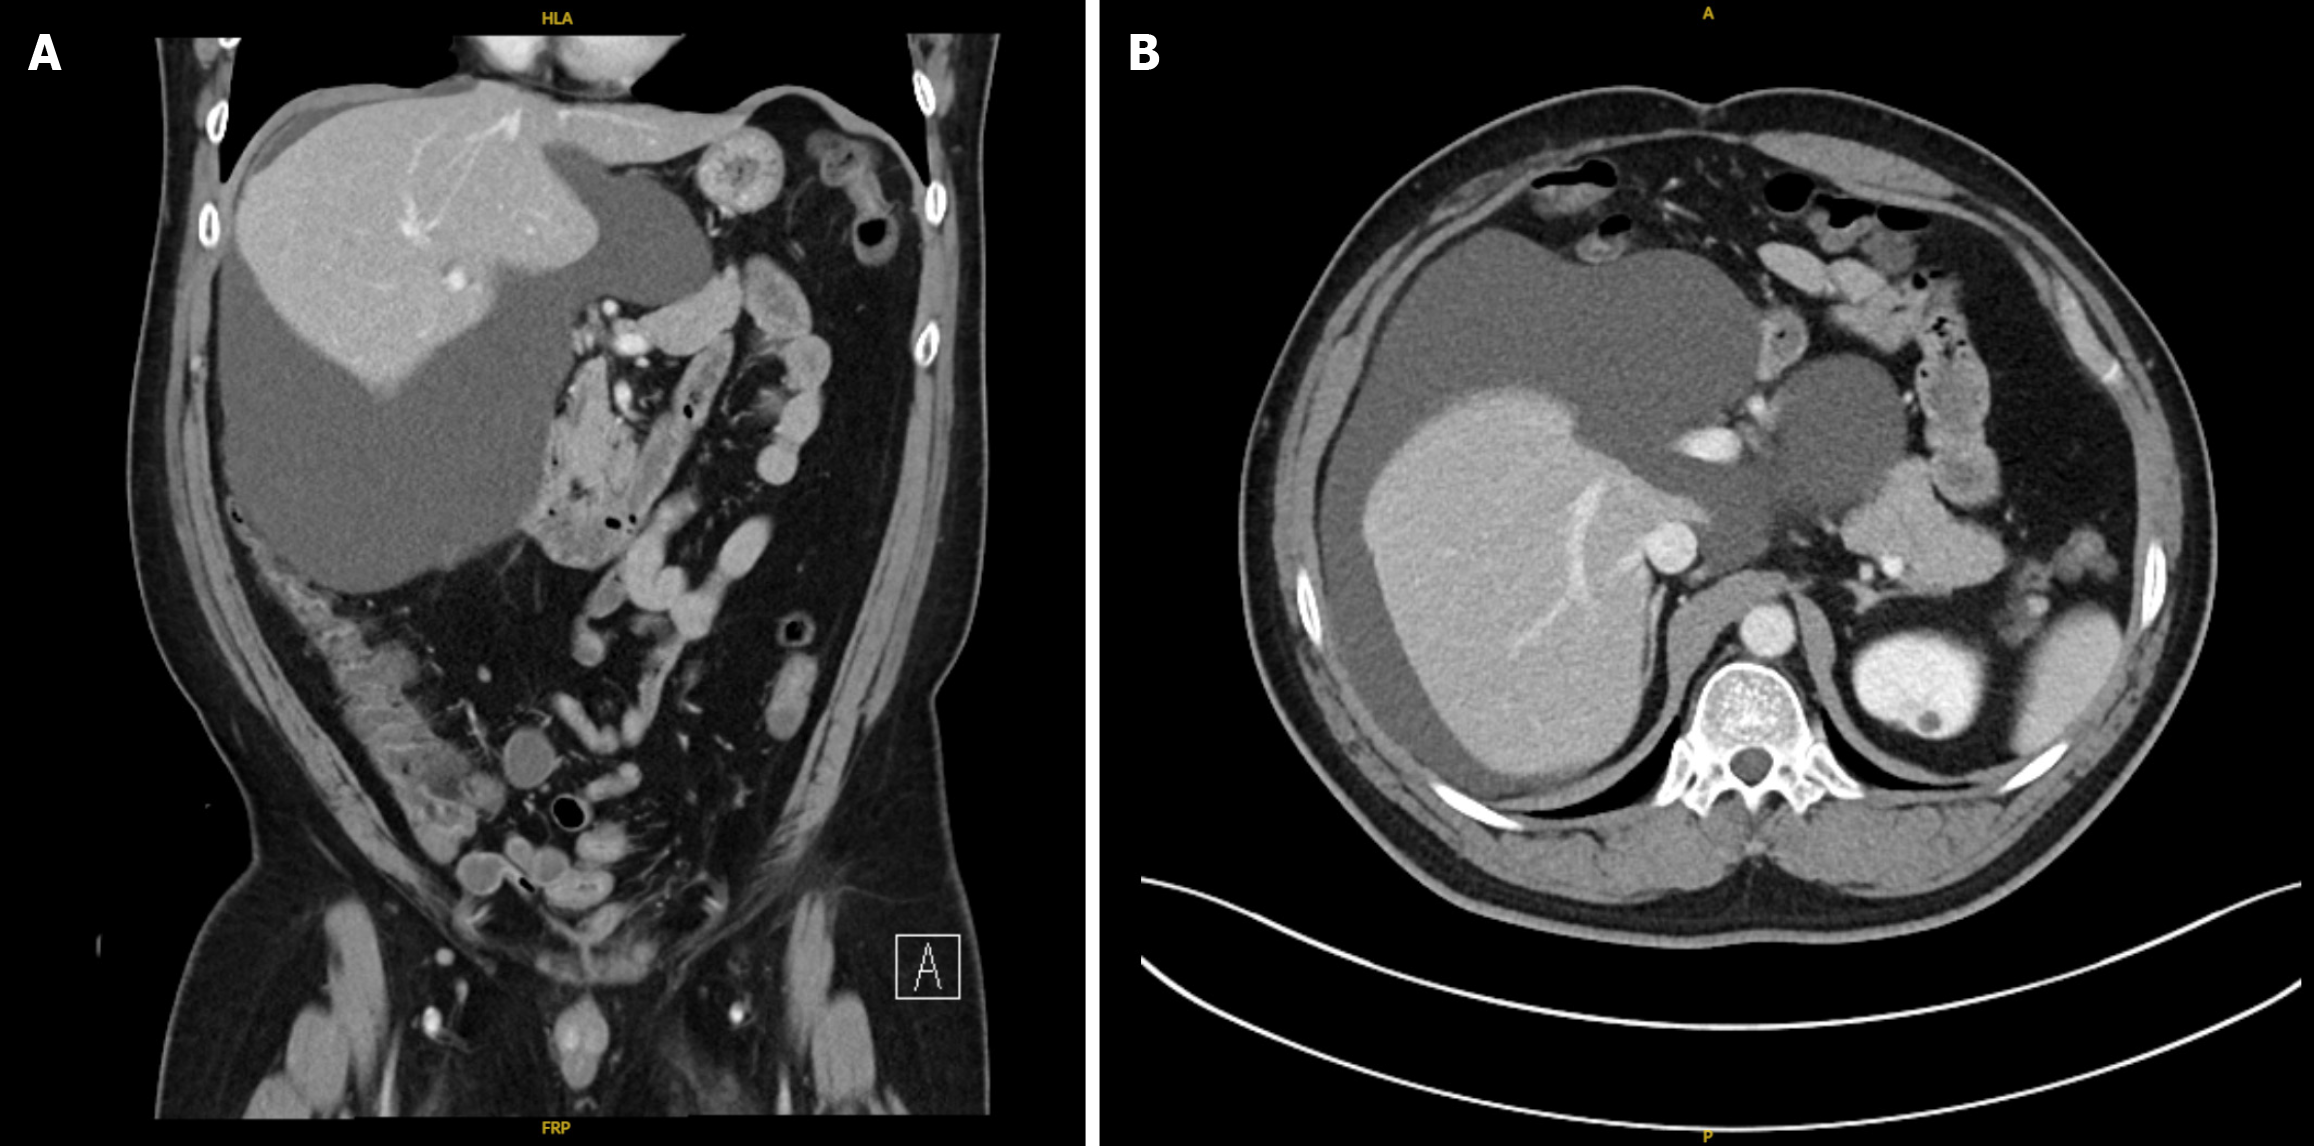

Figure 1 Initial computed tomography of the abdomen and pelvis.

A: Coronal cut; B: Axial cut.